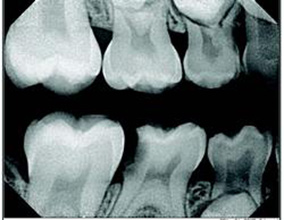

“Digital radiography has positively affected the success of treatment in endodontics. Even the way I schedule procedures changed when I implemented digital X-ray. I used to stop a patient’s treatment to wait on film to be developed, move to another patient until a film was taken there—back and forth, all day. Now, my digital images are on the screen instantly. I can keep working on one patient until the procedure is completed.

This is further improved by the “One-Tooth Series” feature of my digital software. I don’t have to touch the computer at all. The system is ready to capture images throughout the entire procedure.

Digital radiography has a real impact on a patient’s understanding of their treatment. When patients can instantly see their teeth on the screen and watch as I enhance and measure images, they truly understand the reasons for the treatment I deliver (Fig. 2).”